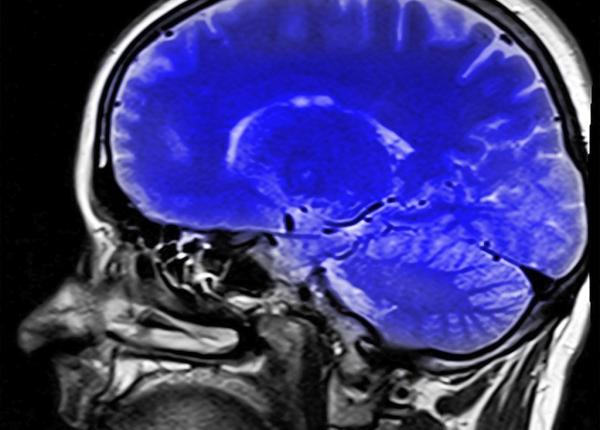

Neurochirurgul Vlad Ciurea, despre coronavirus: „nu atacă un singur organ”

Coronavirus: care este poarta de intrare în organism a virusului